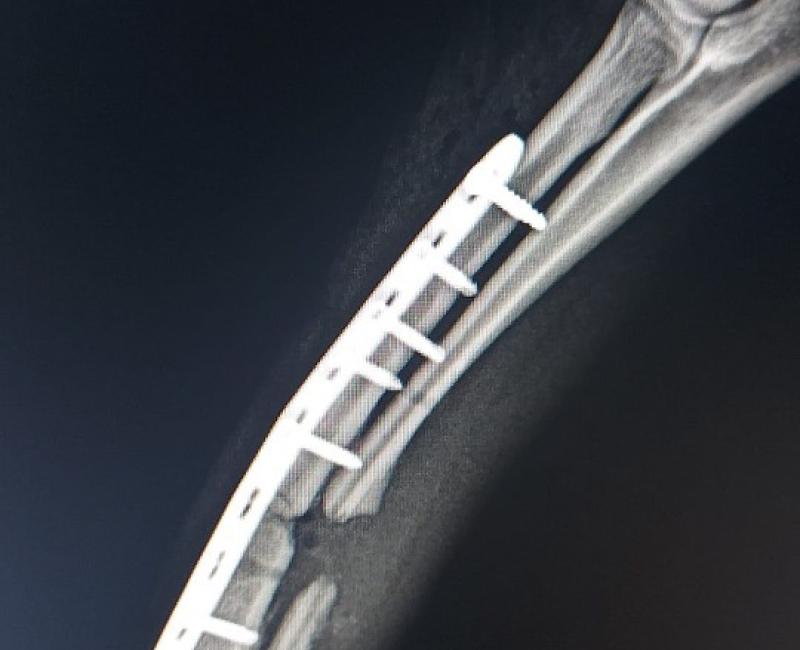

El pequeño ya ha pasado por el veterinario, tiene el cúbito y el radio fracturados. Ha tenido que pasar por quirófano para ponerle una placa y tornillos y ahora se recupera lenta pero adecuadamente.

16 Abril de 2023: Alberto ya ha sido operado, ahora le espera una recuperación lenta pero trataremos de que se le haga lo más amena posible.